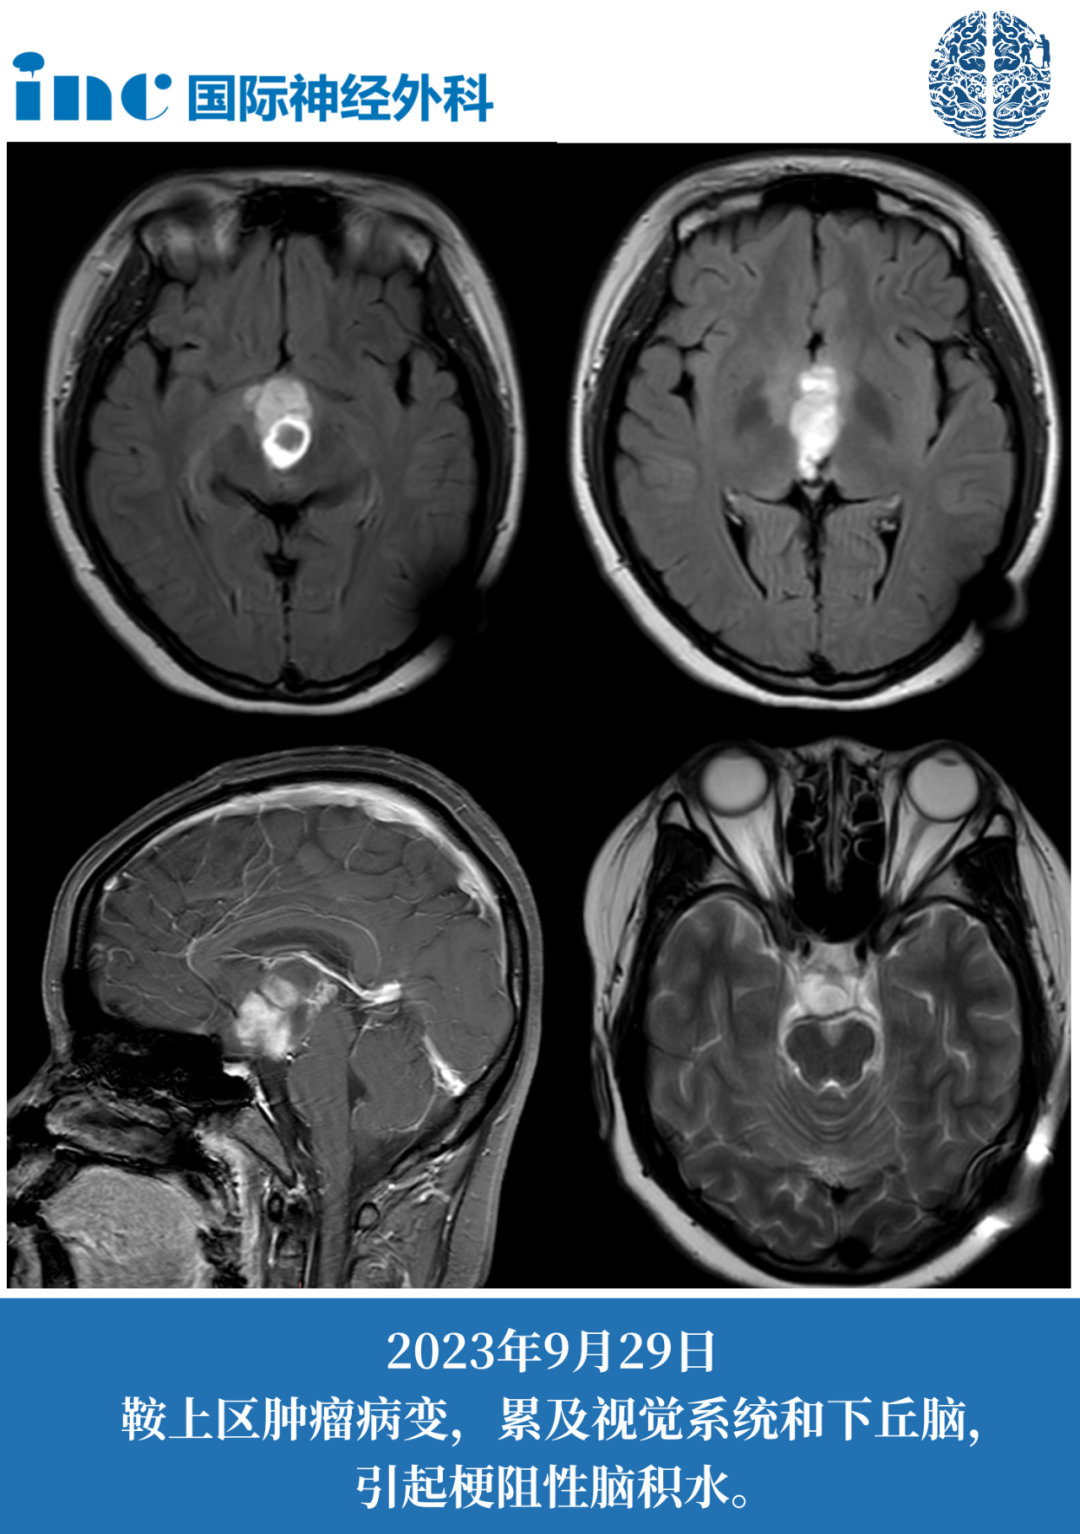

14岁女孩鞍区占位性病变奔赴苏州“我很相信巴教授!”

肿瘤有很明显的占位效应,危及视神经及视交叉(两者已经被肿瘤累及),有明确的手术指征。

手术治疗不能再等,肿瘤一旦进一步增大,小患儿可能面临更严重的问题。

而当下,他们较迫切想要解决的就是手术切除这个伴随孩子长达7年的肿瘤噩梦。

2023年12月妙妙一家远程咨询巴教授,询问目前是否能手术治疗?手术较佳时机?

“现在手术主要目的一个就是要减瘤,减容,取得病理,同时我们要保护她的视力。”

幸运的是,妙妙现在的视力、视野没有受到影响。

巴教授说这是一个好现象——视力越差术中越容易损伤,因为粘越紧。视力越好就越容易把视力保留下来。